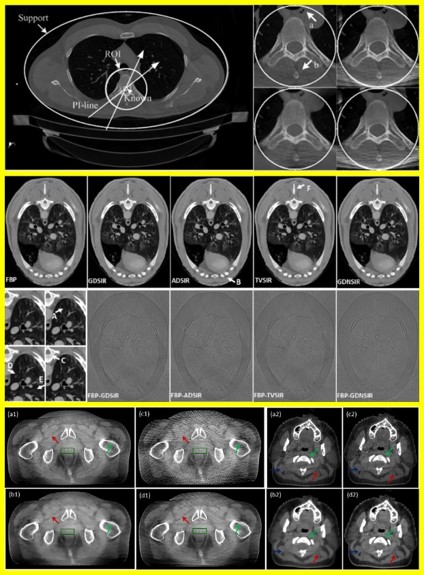

西安交通大学图像处理与识别研究所创立于1983年,隶属于西安交通大学电子与信息工程学院信息与通信工程系,是一所融科学研究和教学为一体,以成像技术、图像处理和模式识别为方向的研究机构,是国内最早在高校设立的图像处理与模式识别领域研究的专业机构之一,首任所长是蔡元龙教授。图像处理与识别研究所(以下简称图像所)建所近30年来,在医学成像、医学图像分析与处理、人类视觉信息获取和分析、视频编码、成像系统的软硬件系统设计与开发等方面具有明显的研究特色和学科优势。得到过20余项 “863计划”和自然科学基金等国家纵向基金项目的支持,其中包括重大项目。团队在理论研究和应用技术开发等方面都有良好的成绩,成果在社会中得到了广泛的应用。 在医学成像领域,我们致力于CT和其它放射成像设备的研发、以及基础算法的研究工作,主要解决医学成像领域关注的低剂量、扫描数据缺失、动态成像、光谱CT和多模态成像等问题。在视觉信息获取和分析领域,我们从视觉神经系统最早期特征的分析出发,从多个层面对图像质量评价和视觉观察者模型等问题开展了研究工作,提出了一系列高效率的计算模型,开发了图像质量感知主观评测数据库,开展了基于图像质量感知模型的视频/图像压缩编码技术研究,开发了与上述相关的软硬件系统。在光谱成像领域,研制的静态高光谱全偏振成像仪是首台基于通道调制和双折射干涉仪的静态高光谱全偏振成像仪。